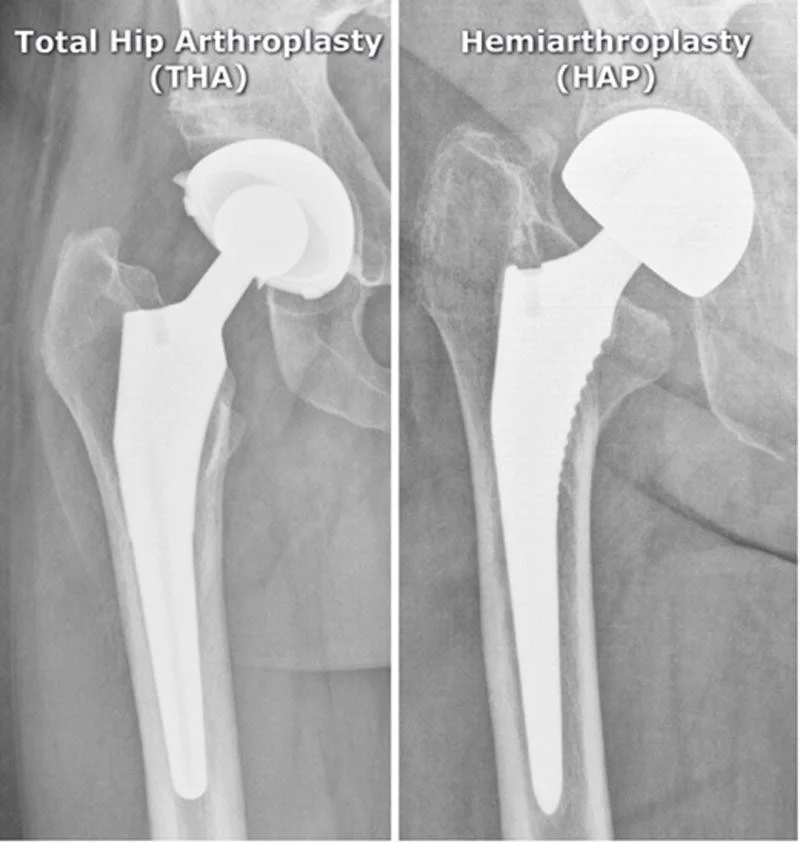

Arthroplasty

- Total Hip Arthroplasty (THA)

- Hemiarthroplasty (HAP)

Infected Arthroplasty

- Pain after arthroplasty

- Mild fever

Infection hemiarthroplasty

- vague periprosthetic bone resorption

- periosteal reaction

- cement

Normal

- hemi-arthroplasty